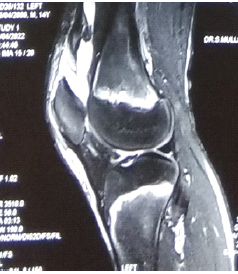

Arthrex Labral Scorpion for Anterior Cruciate Ligament Repair: A Novel Application for this Instrument: Case Report

Vanessa C Heck , Logan Van Poucke , Holly C Heck , Alex D Keith , Brian Holmes , Bruce E Heck